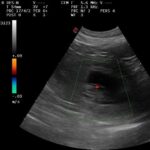

Am 22.01.20265 waren wir mit Ilarya Vom Diepmannsbachtal zur Trächtigkeitsuntersuchung in Dortmundunser. Dabei wurden 9-10 Fruchtanlagen gezählt. Wir freuen uns jetzt auf eine weiterhin ruhige Trächtigkeit und eine gute Geburt! Zur…